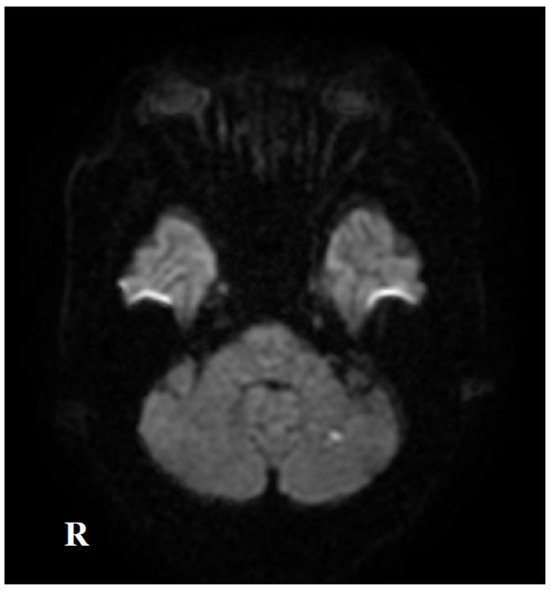

2. Case Presentation